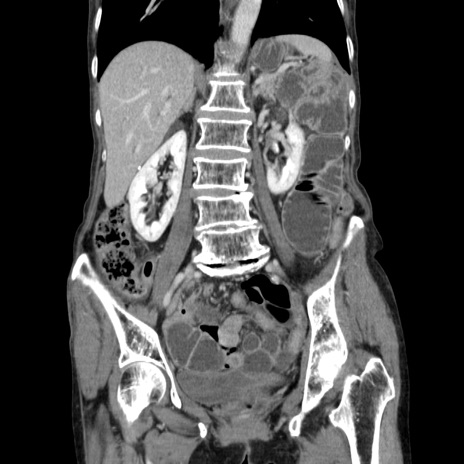

症例25(冠状断像)

【症例】80歳代女性

【主訴】胸のつかえ感

【現病歴】約9時間前に食後から胸のつかえた感じあり、嘔吐あり、来院。

【既往歴】胃癌(全摘)、胆摘、虫垂炎

【身体所見】心窩部に圧痛あり、反跳痛なし。

【データ】WBC 5700、CRP 0.05